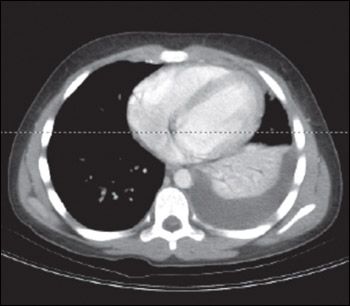

Figure 1 – This patient's chest CT scan showed a left-sided pleural effusion with consolidation. The cause of the pneumonia was invasive group A streptococcal infection.

A complete blood cell count reveals a white blood cell count of 21,500/μL, with a left shift (41% neutrophils, 17% band forms, 25% lymphocytes, 3% basophils, and 4% eosinophils). Liver transaminase levels are elevated (aspartate aminotransferase, 217 U/L; alanine aminotransferase, 398 U/L). Titers of anti-DNAse B and anti-streptolysin O (ASO) are markedly positive (ASO level, 1298 UI/mL). Culture of joint fluid obtained via arthrocentesis of the left knee grows group A β-hemolytic streptococci (Streptococcus pyogenes). Chest CT scan reveals a leftsided pleural effusion with consolidation (Figure 1).

Invasive, disseminated group A streptococcal (GAS) infection is diagnosed. Manifestations of the infection include left periorbital cellulitis with associated sinusitis, left-sided pneumonia with a parapneumonic effusion, and septic arthritis of the left knee.